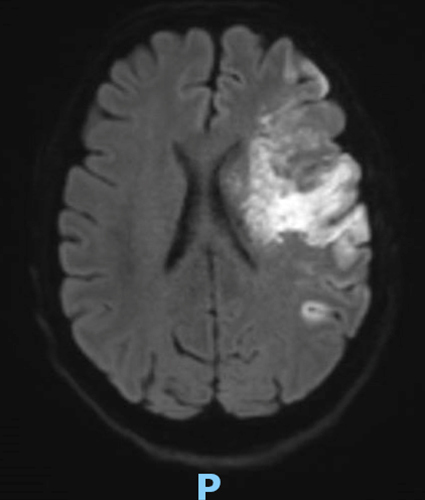

Le type d’hémianopsie est très important car il permet de localiser une atteinte neurologique, en connaissant le trajet des voies optiques.

Cette question supposait d’avoir bien en tête le schéma des voies optiques, et d’avoir des repères sur les principaux territoires vasculaires cérébraux et l’atteinte clinique associée. Il bien mentionné par le CEN que l’hémianopsie latérale homonyme gauche peut se voir dans un AVC sylvien superficiel droit.

Tableau d’après le Collège des enseignants de neurologie. Altération aiguë de la vision.